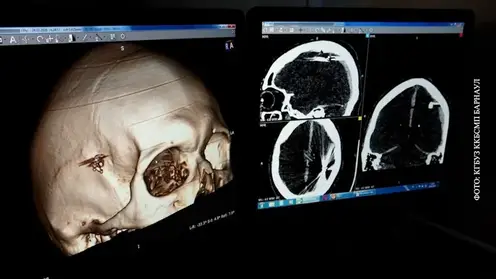

Мальчику из Кузбасса с разрезанной отчимом губой провели пластическую операцию